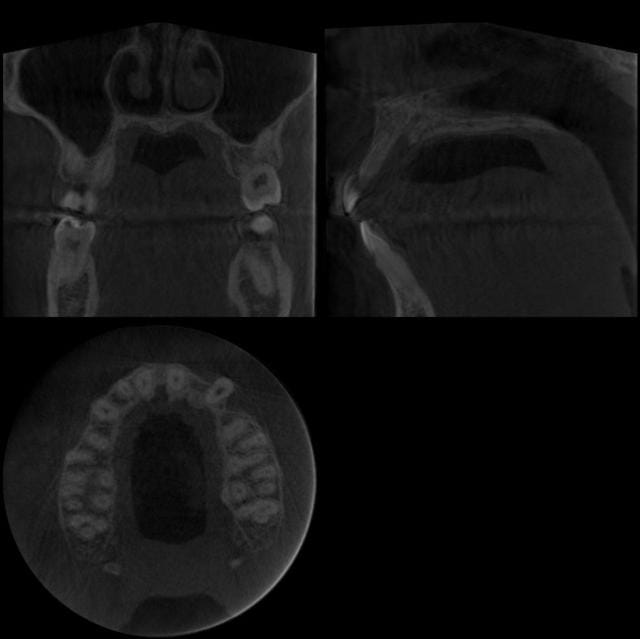

13/03/2007 à 08h25

Et voilà